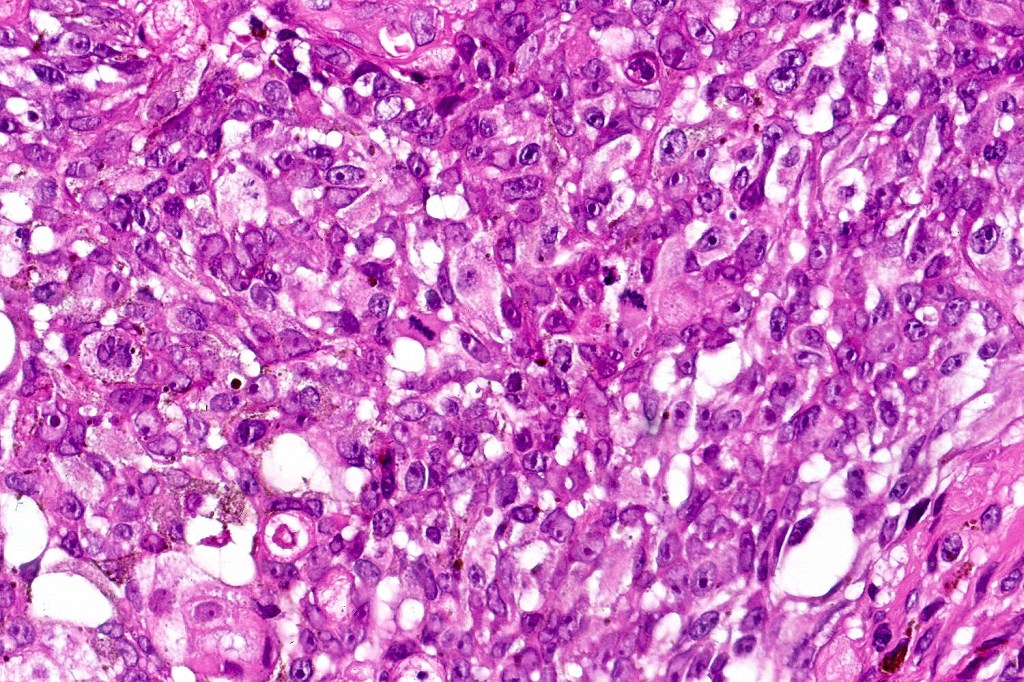

•Basaloid population with prominent nucleoli accompanied by supramatricial and ghost cells

•Variable pleomorphism

•Mitoses may be conspicuous

•Heavily pigmented dendritic +/- epithelioid melanocytes

Melanocytic matricoma should be differentiated from pigmented pilomtricoma. This is much nore common and is characterized by pigmented dendritic cells and pigmented matrical cells in the abscence of any mitotic activity or pleomorphism in the melanocytic population. However, there can be considerable overlap.

Dendritic cells are not a feature of matrical carcinoma. Pleomorphism & mitotic activivty is much more pronounced in the latter and perineural infoltration and/or lymphovascular invasion/necrosis may also be present.